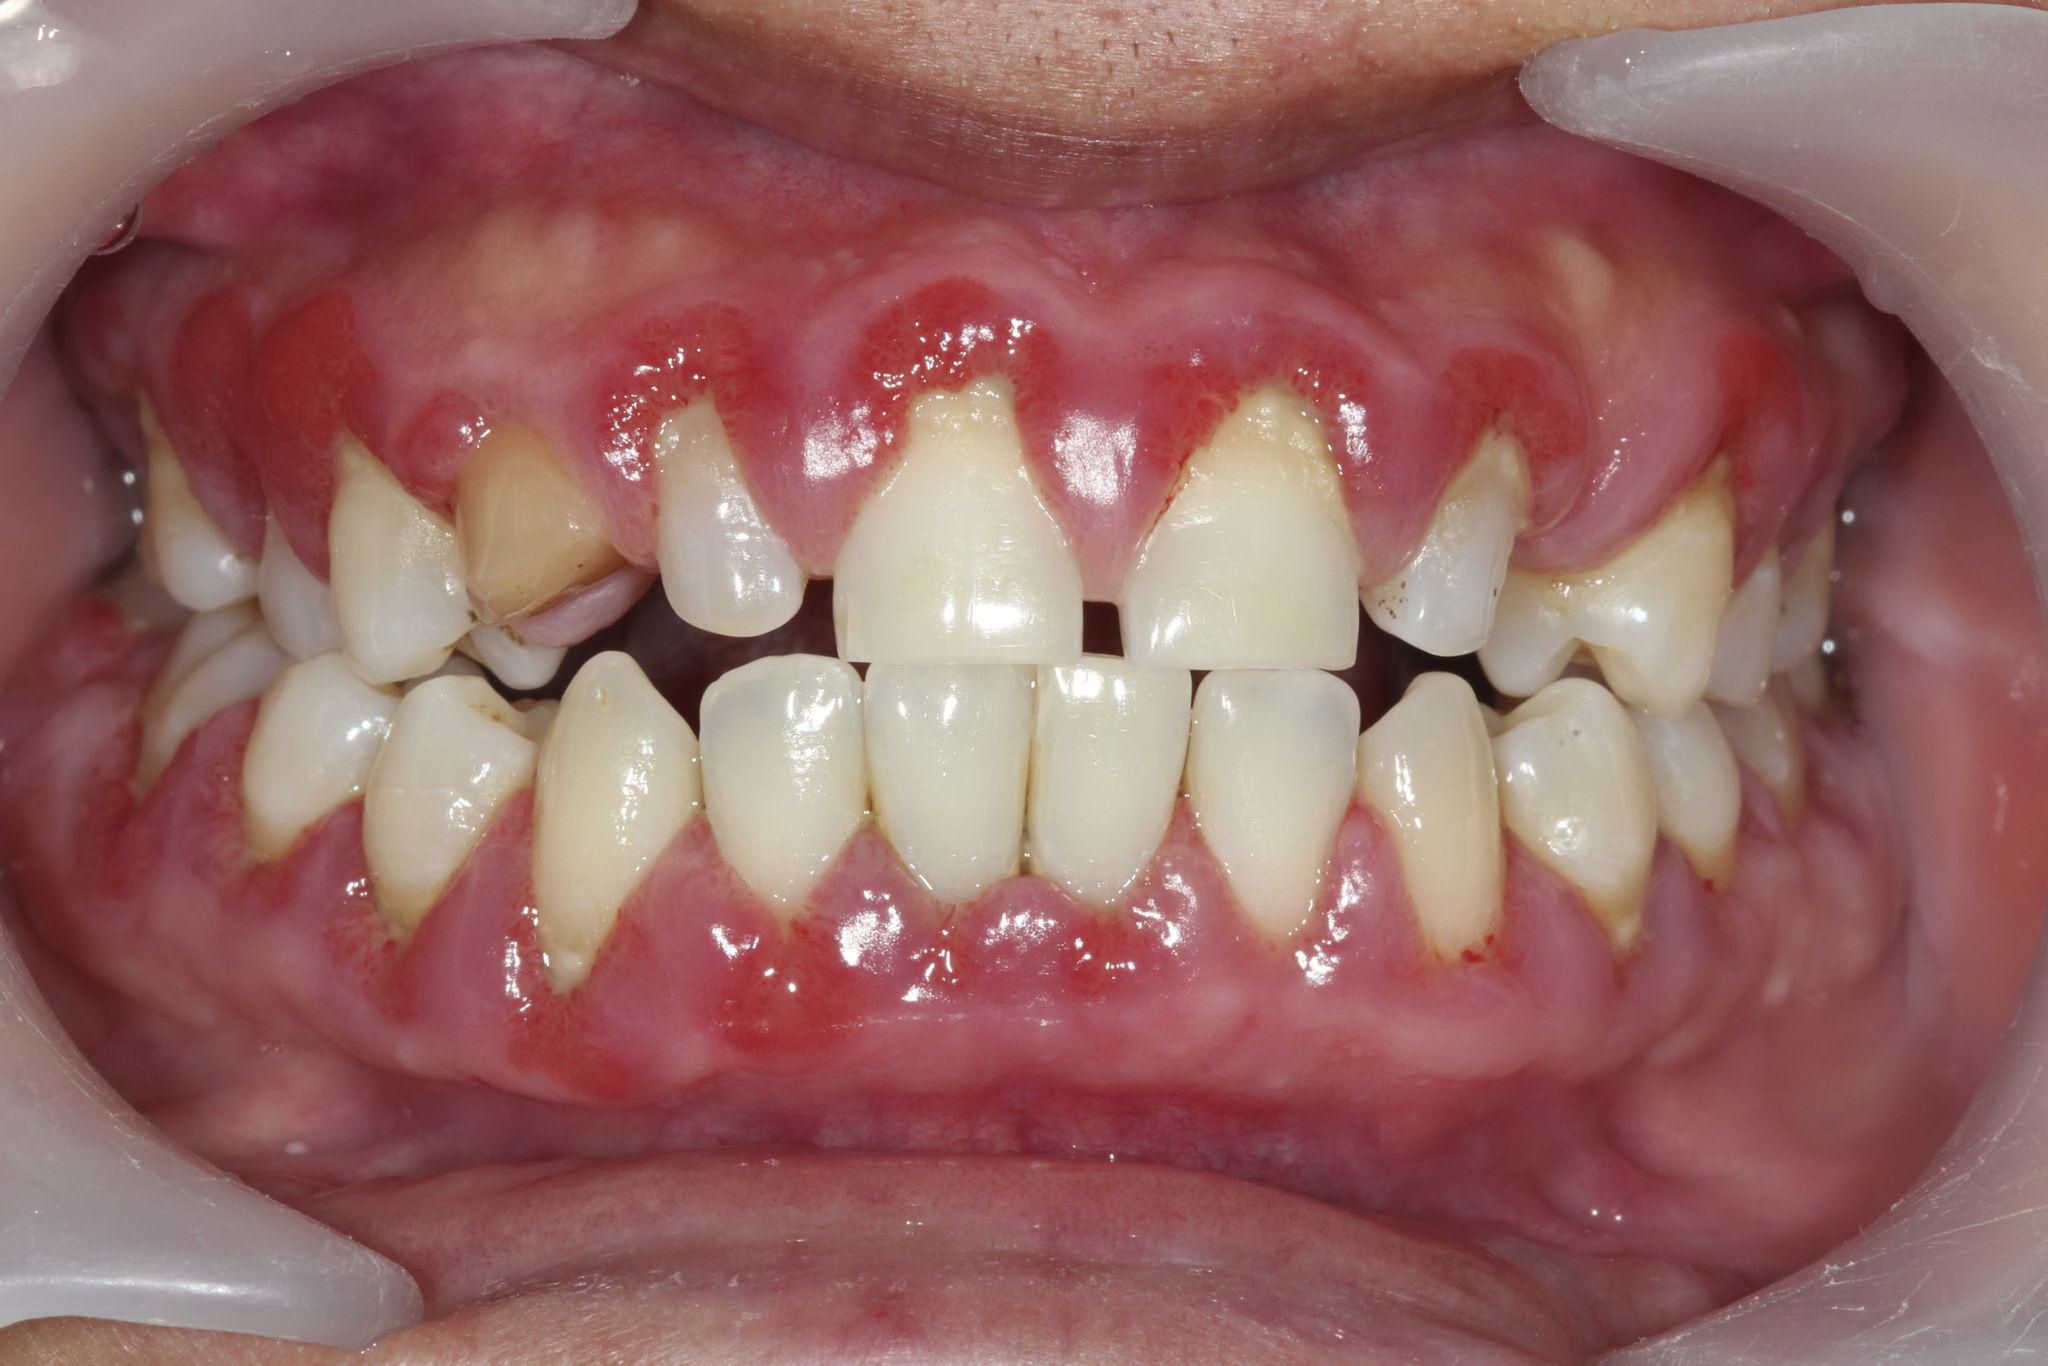

Understanding Periodontal Disease

Before treatment comes understanding.

You will develop a deep knowledge of:

- The etiology of gingivitis and periodontitis

- The role of plaque biofilm and calculus

- Risk factors including systemic conditions

- The oral-systemic health connection

- Stages and grading of periodontal disease

This scientific foundation allows you to support accurate diagnosis and effective treatment planning.

Periodontal Examination & Charting

Precision matters in periodontics.

You will learn to:

- Assist during comprehensive periodontal evaluations

- Understand probing depths and attachment loss

- Recognize bleeding indices and mobility

- Support radiographic interpretation

- Accurately document findings

Clear and accurate periodontal charting is essential for both patient care and legal protection.